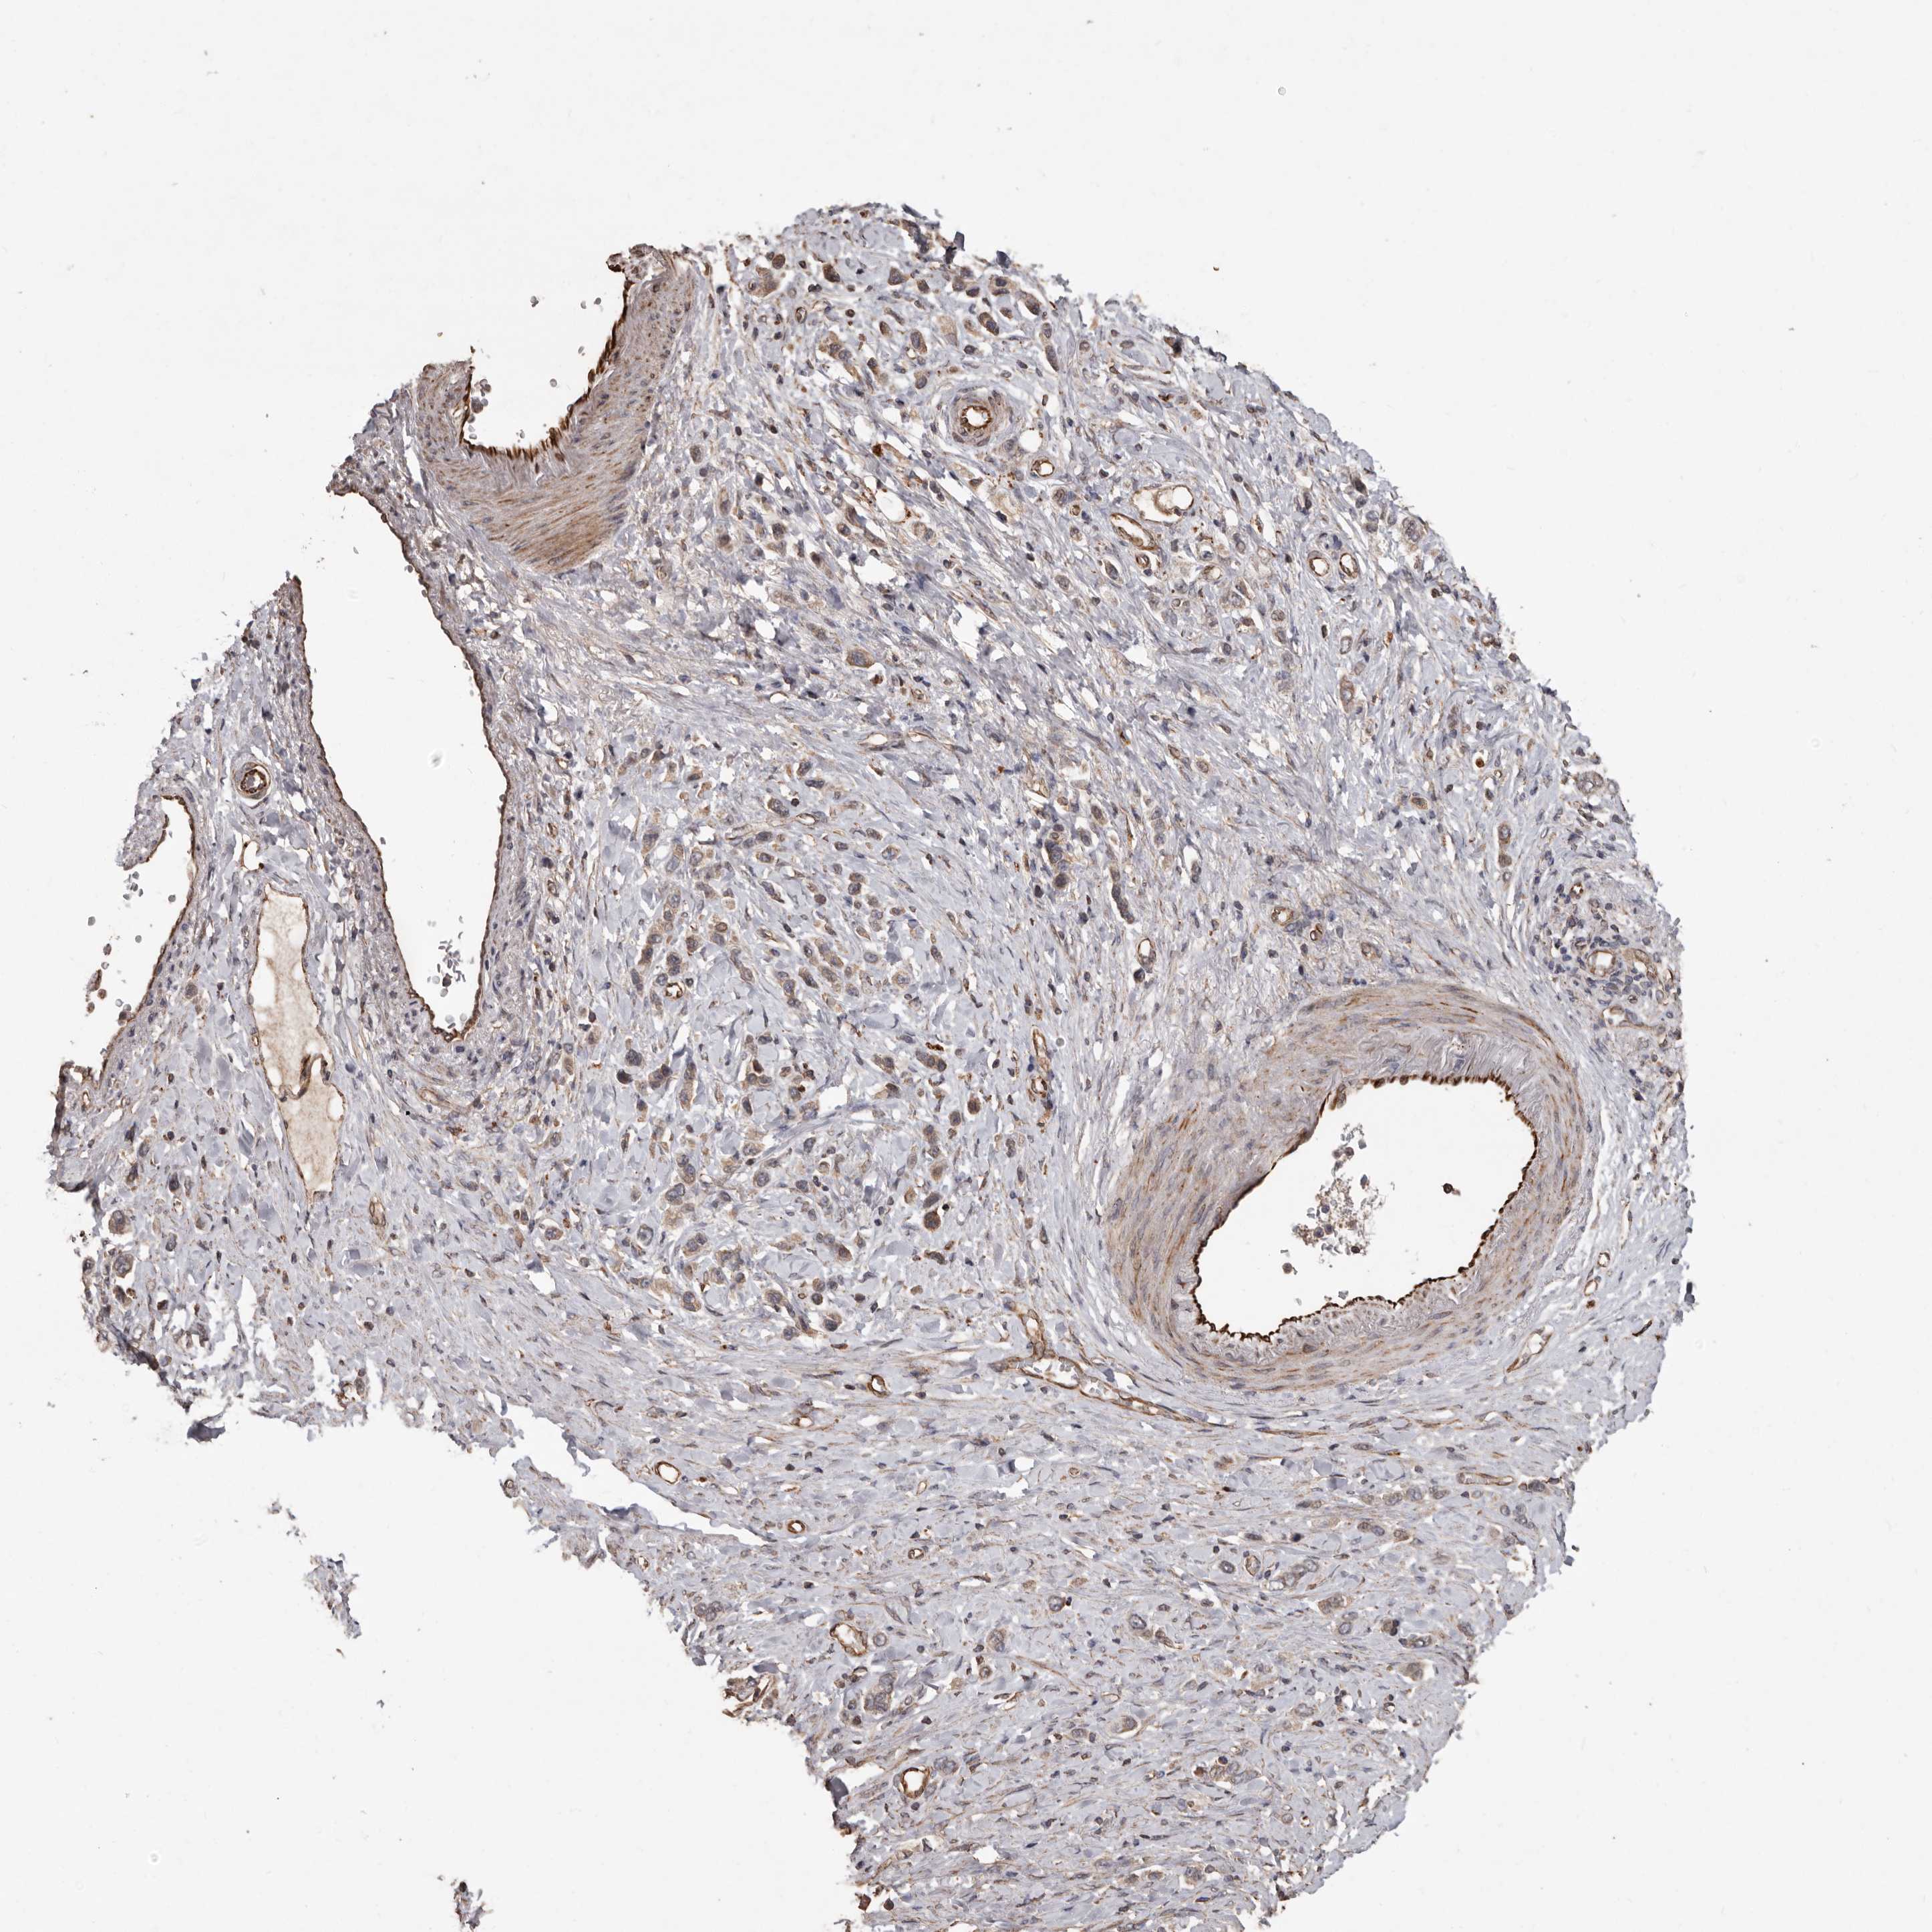

STOMACH CANCER - Protein expressioni

A mouse-over function shows sample information and annotation data. Click on an image to view it in a full screen mode. Samples can be filtered based on level of antibody staining by selecting one or several of the following categories: high, medium, low and not detected. The assay and annotation is described here.

Antibody stainingi

Antibody staining in the annotated cell types in the current human tissue is reported as not detected, low, medium, or high, based on conventional immunohistochemistry profiling in selected tissues. This score is based on the combination of the staining intensity and fraction of stained cells.

Each image is clickable and will lead to virtual microscopy that enables deeper exploration of all samples and also displays staining intensity scores, fraction scores and subcellular localization as well as patient and tissue information for each sample.

Antibody HPA029455

Staining

High

Medium

Low

Not detected

Intensity

Strong

Moderate

Weak

Negative

Quantity

>75%

75%-25%

<25%

None

Location

Nuclear

Cytoplasmic/membranous

Cytoplasmic/membranous,nuclear

Adenocarcinoma, NOS